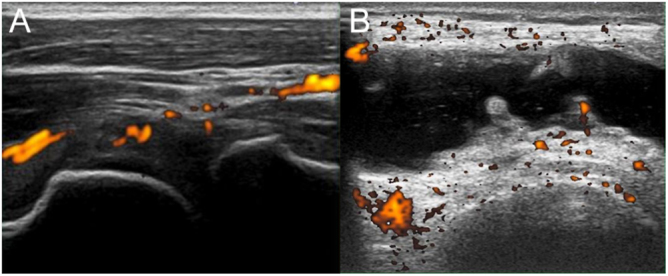

Summary: Hypophosphatasia (HPP) is a genetic disorder due to pathological variants in ALPL, the gene encoding tissue-nonspecific alkaline phosphatase (ALP). HPP is typically associated with bone-related symptoms, such as bone deformity, fractures and bone pain in children, but can appear in adults with symptoms resembling arthritis. A 22-year-old male experienced repeated and severe sudden attacks of joint pain in the elbows and knees. Magnetic resonance imaging and joint ultrasonography showed joint effusions indicating chronic inflammation. Blood biochemical tests revealed a remarkably low serum ALP level, and repeated examination confirmed a sustained low ALP level; urine phosphoethanolamine, plasma inorganic pyrophosphate and plasma pyridoxal-5'-phosphate levels were elevated, raising concern for HPP. While the patient had no history of premature loss of primary teeth, fragility fractures, muscle weakness or abnormalities in growth, genetic testing revealed a likely pathogenic and a pathogenic heterozygous variant in the ALPL gene, i.e., c.979T>C (p.Phe327Leu) and c.1559del (p.Leu520Argfs), confirming HPP. Additional genetic testing of his parents showed a heterozygous c.1559del variant in his father and a heterozygous c.979T>C variant in his mother. A diagnosis of adult HPP due to compound heterozygous mutations was therefore confirmed. Enzyme replacement therapy with asfotase alfa was then introduced; no attacks of arthralgia occurred in the 1-year period since then. This case highlights the possibility of HPP in adults who present clinically with repeated joint symptoms and low serum ALP levels but without bone-related symptoms.